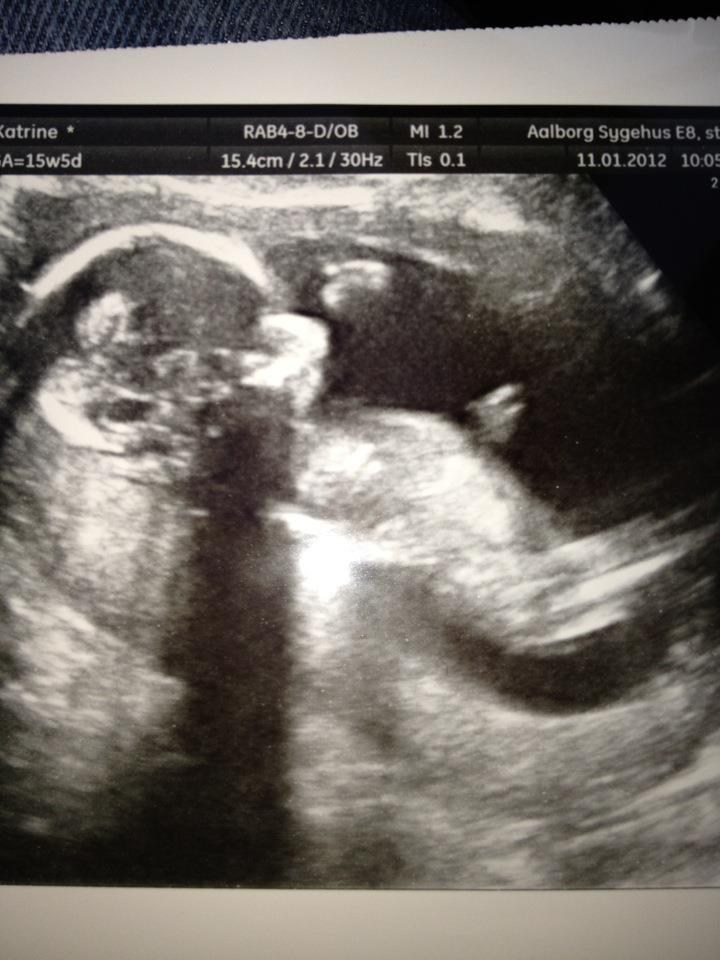

Scanningen gik bare rigtig fint og vores baby pige vokser, som hun skal - måler næsten 16 cm

Jeg er selv 15+5 idag

I får lige et par billeder med af vores dejlige Prinsesse